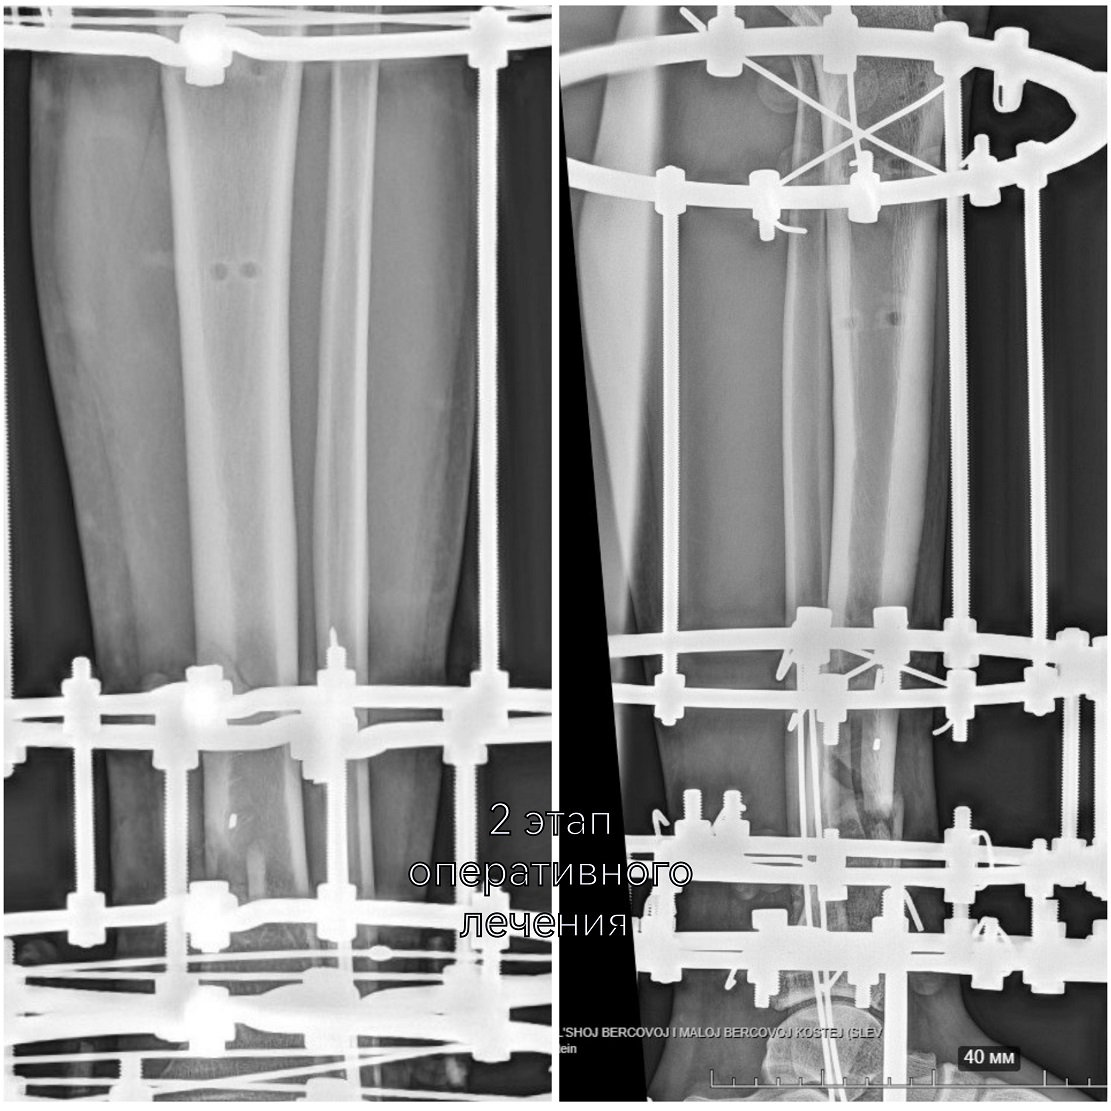

Цель первого этапа хирургического лечения - жизнеспособность конечности – была достигнута. Цель второго этапа – опороспособность. К нему приступили, убедившись, что ранний послеоперационный период протекает благополучно, без осложнений.

-На втором этапе первично установленный стержневой аппарат демонтирован и выполнен окончательный остеосинтез аппаратом Илизарова. На сегодняшний день это самый надежный и управляемый вариант. Данный вид фиксации позволяет проводить раннюю реабилитацию и передвигаться с нагрузкой на поврежденную ногу. Послеоперационный период проходит спокойно, мужчине назначено комплексное восстановительное лечение, включающее физиотерапевтические процедуры и занятия ЛФК, - объясняет лечащий врач Юрия, травматолог-ортопед Артём Мещеряков, выполнивший второе вмешательство.